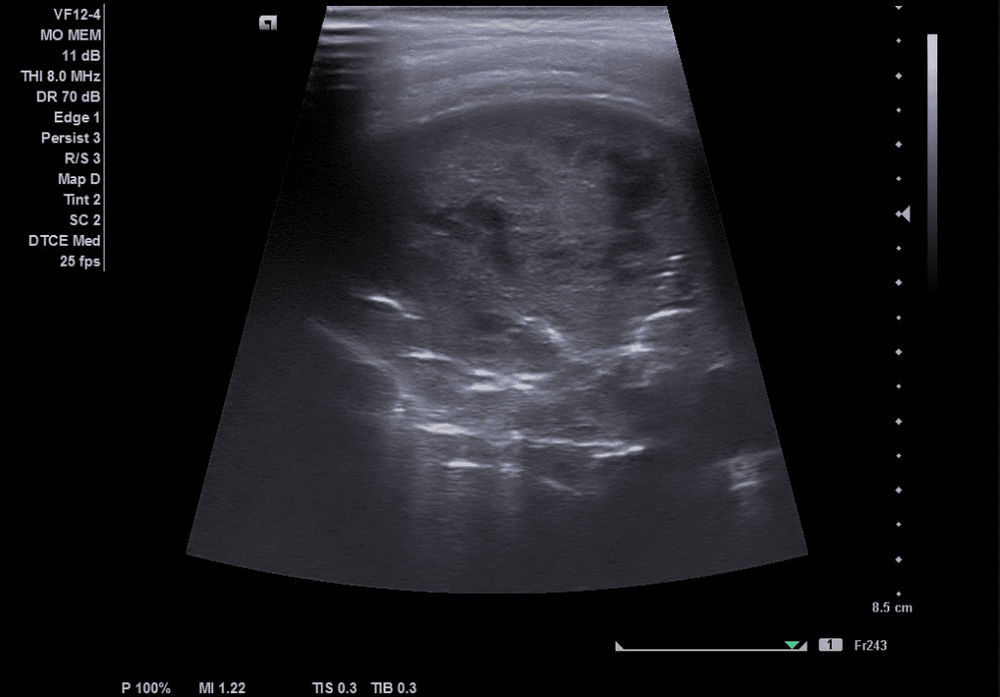

Siêu âm phổi là phương pháp chẩn đoán hình ảnh sử dụng sóng siêu âm để quan sát và tái hiện hình ảnh cấu trúc phổi. Đầu dò siêu âm sẽ được đặt ở các vị trí nhất định tương ứng với vị trí của phổi để ghi lại hình ảnh thu được trên màn hình hiển thị. Qua đó, các bác sĩ sẽ xác định được tình trạng phổi, chẩn đoán các bệnh lý về phổi như: viêm phổi, khí trong nhu mô phổi, đông đặc phổi, tràn khí màng phổi...

Siêu âm phổi là phương pháp an toàn và cho kết quả có độ chính xác cao. Siêu âm phổi cho phép tái hiện cấu trúc phổi, từ đó xác định trẻ có bị viêm phổi hay không, mức độ viêm phổi nặng hay nhẹ.

Khi đã có chẩn đoán xác định viêm phổi, từ hình ảnh siêu âm có thể thấy phổi của trẻ có hình ảnh đông đặc phổi hay những ổ đông đặc rải rác hay không. Đó là biểu hiện của tình trạng viêm phổi thùy hoặc viêm phổi lan tỏa. Nhiều trường hợp trẻ bị viêm phổi không có những biểu hiện rõ rệt, trẻ không ho nhưng lại có triệu chứng đau bụng và sốt. Siêu âm kiểm tra ổ bụng có thể phát hiện hình ảnh đông đặc đáy phổi, giúp xác định chính xác tình trạng bệnh của trẻ.